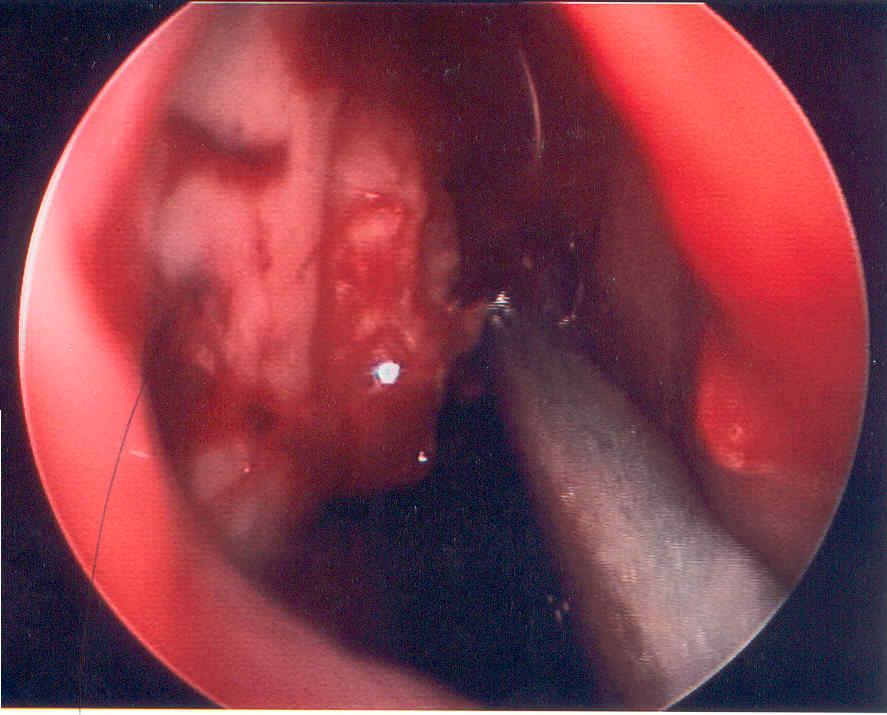

In the same patient the middle turbinate has been resected to reveal the middle meatus lateral to it.  The uncinate and bulla ethmoidalis are blanched and necrotic as well.

The patient's middle tubinate and right lateral nasal wall were debrided.

She lived to survive this life threatening event.